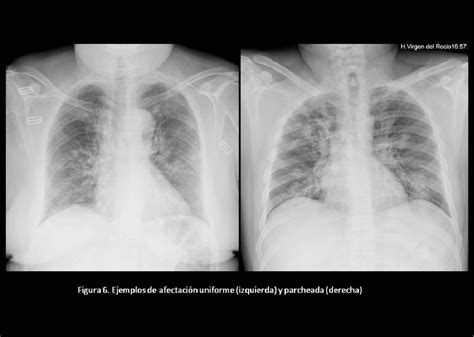

La mayoría de las guías nacionales e internacionales realizan diagnóstico clínico de NAC y confirmación radiológica de la misma, a excepción de la British Thoracic Society (BTS).

A pesar, de que la mayoría de los LR + evaluados no fueron significativos o fueron de utilidad en pacientes que cumplían con criterios de gravedad, todas las guías plantean diagnóstico clínico con confirmación radiológica, a excepción de la BTS que no utiliza imágenes de rutina.